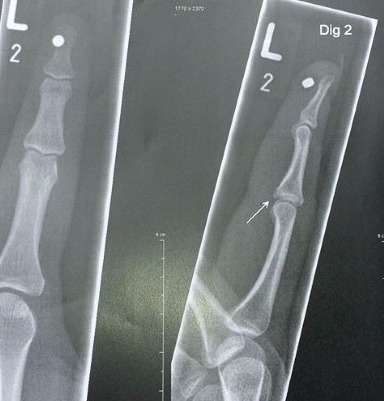

Eine recht neue und faszinierende Möglichkeit der Modifikation bieten Magnetimplantate, welche vorzugsweise, aber nicht ausschließlich im Finger platziert werden. Die Einsätze bestehen aus hochwertigen Neodyme-Magneten welche mit einer strapazierfähigen Silikonummantelung überzogen sind. Auch hier gibt es verschiedene Ausführungen in Größe und Legierung. Die Möglichkeiten mit Magneteinsätzen sind ebenso Vielfältig wie genial, jedoch sollte man sie nicht in Chipnähe lassen!